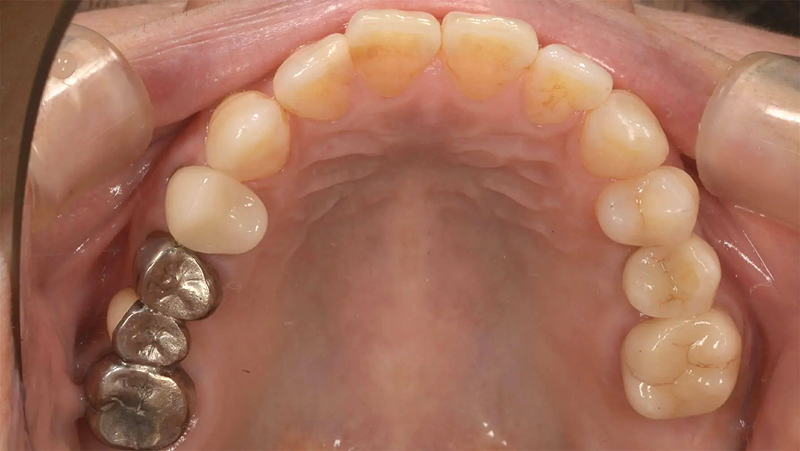

Case03部分矯正とインプラントで歯列を整えた症例

メインテナンスに通っていた患者さんであるとき、左上第2大臼歯のかぶせ物が脱離して来院されました。第2大臼歯は歯根破折をしており、残念ながら予後不良で抜歯と診断しました。元々、第2小臼歯が欠損しており、第1大臼歯がそのスペースに倒れこんでいる歯列不正がありました。この機会に歯列を整えて、インプラントをしましょうと提案しました。承諾していただき、5か月の部分矯正後、インプラントを埋入しました。3年経ちましたが経過は順調です。

左上7番 歯根破折 ⇒ 抜歯 左上6番 部分矯正開始 2016.2.8

左上6番 部分矯正終了 2016.7.12 ファイナル 2016.9.27

治療後3年 2019.10.12